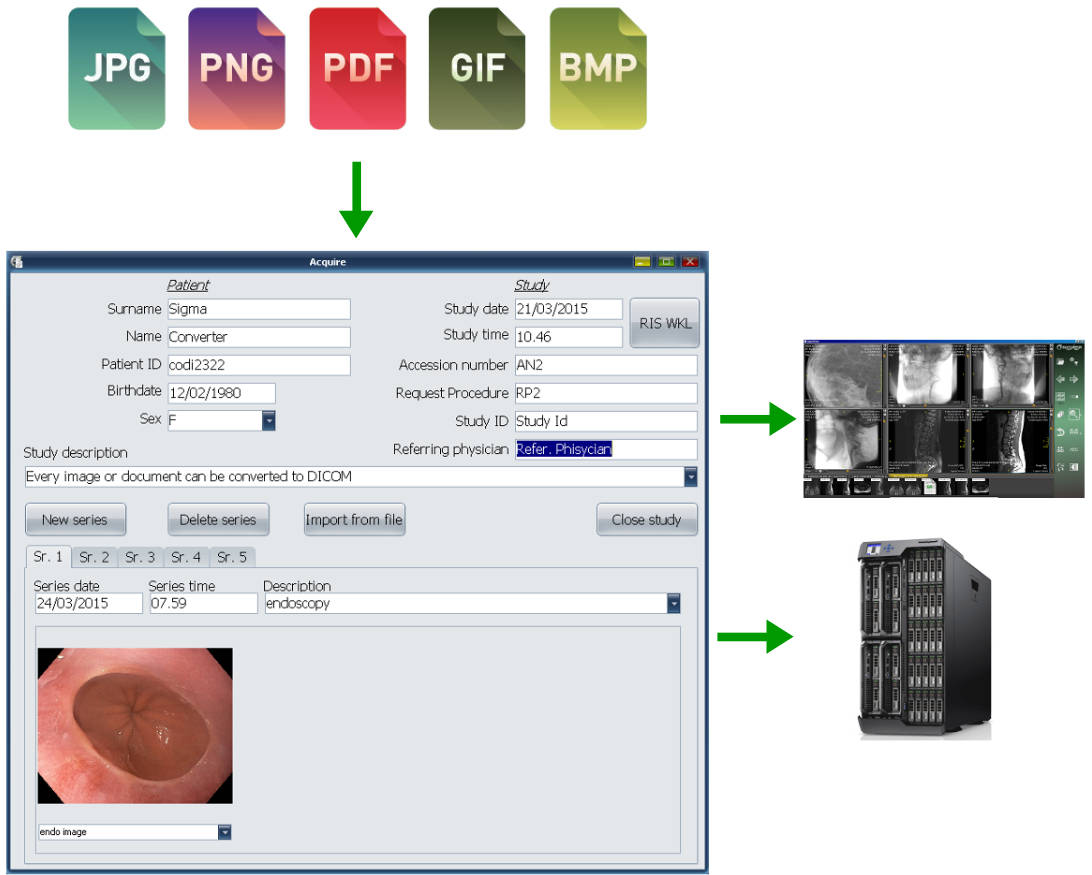

Лазерная камера для печати медицинских изображений на пленке стандарт dicom